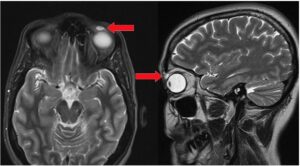

diverse 32 de cazuri medicale neobișnuite 3 iunie 2024 by Echipa Club S&T | Leave a Comment Două scanări ale creierului (una din vârful capului femeii și una din lateral) arătând micul chist din pleoapa ei. Săgețile roșii indică chistul. (Credit imagine: BMJ Case Reports 2018) Corpul uman continuă să surprindă medicii, care raportează că au întâlnit pacienți cu afecțiuni rare sau abilități unice. În această listă, aruncăm o privire la 32 […] Read more »